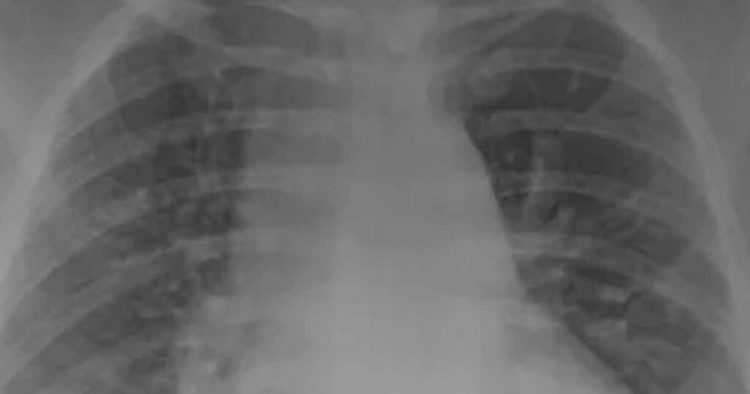

Dr Ghassan Kamel zajmujący się chorymi na COVID-19 w SSM Health Saint Louis University Hospital w Missouri, postanowił pokazać w jaki sposób działają szczepionki na nasze płuca. To zdjęcie RTG przedstawia płuca osób chorujących na COVID-19. Zasadnicza różnica jest taka, że jeden z pacjentów jest zaszczepiony, drugi natomiast nie.

To już kolejna próba zachęcenia ludzi do przyjmowania szczepionek. Amerykański lekarz postanowił wszystkim pokazać jak wyglądają płuca osoby zaszczepionej, która zachorowała na COVID-19 orazosoby która również zachorowała, ale preparatu nie przyjęła. Różnica jest naprawdę spora. Na zdjęciu RTG osoby, która nie przyjęła preparatu widoczne są duże zmiany.

Zdjęcie RTG przedstawia płuca osoby zaszczepionej i niezaszczepionej

Ten mleczny cień widoczny na zdjęciu RTG oznacza zmętnienie płuc co oznaczać może bardzo ciężki przebieg choroby oraz możliwość wystąpienia również innych dolegliwości wymagających opieki lekarskiej.Zazwyczaj pacjent z takimi zmianami ma problemy z oddychaniem. Tacy również najczęściej potrzebują respiratora w przebiegu choroby.

Zdjęcie osoby która przyjęła szczepionkę na COVID-19 nie widać żadnych większych zmian. Amerykański doktor jest przekonany o swojej racji i zachęca wszystkich, którzy się jeszcze nie zaszczepili do tego aby to zrobili.

„Mogą wymagać respiratora lub zostać zaintubowani i zasadniczo podtrzymywania życia. Jeśli nie lubisz nosić maski to z pewnością nie spodoba ci się respirator” – przekazuje Kamel dla stacji KSDK.